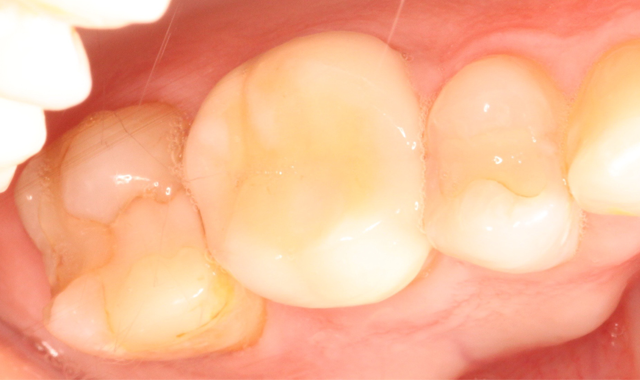

Fig. 1 Fig. 2

A 53-year-old male presented with a treatment plan to replace an existing f rst molar crown and prepare a crown on a second molar (Figs. 1-2).

The patient was anesthetized and tolerated the crown preparations well. Both zirconia-style preparations were digitally scanned and those scanned impressions were sent to an off-site lab. Temporary crowns were fabricated and worn for two days. Upon return, the temporary crowns were immediately removed. Notice the healthy condition of the gingiva (Fig. 3).